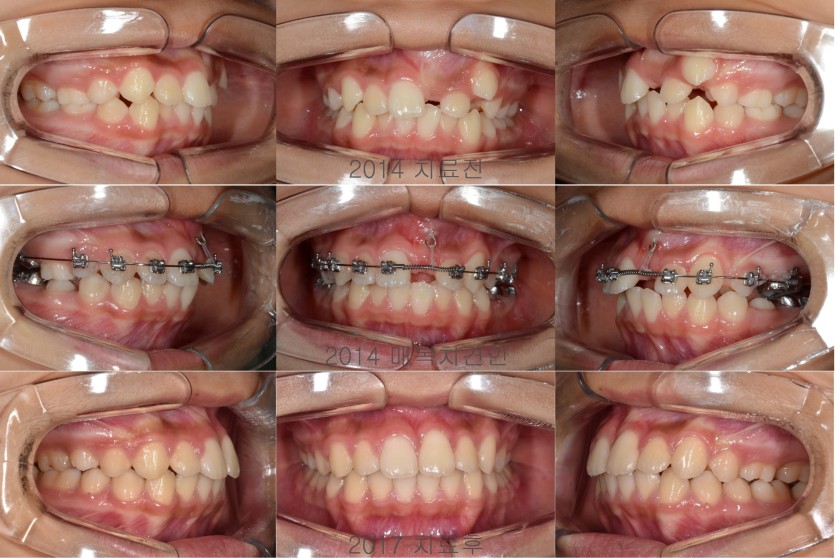

매복된 상악 중절치의 견인치료 137회

여러가지 이유로 매복된 치아들은 견인의 방법으로 해결해야 합니다.

매복된 치아들을 견인하기 위해서는 잇몸을 열어서 장치를 부착해야하는 소수술이 필요합니다.

장치를 부착하고 천천히 견인하되 견인방향과 배열을 위한 공간확보에 대한 고려가 필요합니다.